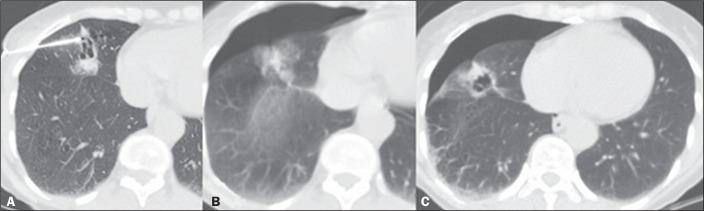

To assess the diagnostic success rate and complications of computed tomography (CT)-guided percutaneous biopsy in pulmonary nodules < 10 mm in diameter.

This was a retrospective, single-center study involving the review of medical records, images, and chest CT reports related to 115 patients who underwent percutaneous CT-guided biopsy of < 10 mm pulmonary nodules between July 2015 and January 2019.

Nodule diameter on the longest axis ranged from 4 mm to 9 mm, with a mean size of 7.7 mm. The mean age of the patients at the time of the procedure was 61 years, and 54.7% were women. Of the 115 nodules evaluated, 77 (67.0%) were solid and 55 (47.8%) were located in the lower lobes. The mean distance traversed by the needle in the lung parenchyma was 20 mm (range, 0-70 mm), and, in most cases, the biopsy was not performed with the patient in the biopsy-side-down lateral position. The diagnostic success rate was 93.0%. The most common complications were alveolar hemorrhage (in 36.5% of cases) and pneumothorax (in 24.3%).

The data suggest that CT-guided percutaneous biopsy of < 10 mm pulmonary nodules has a high diagnostic success rate and an acceptable rate of complications.